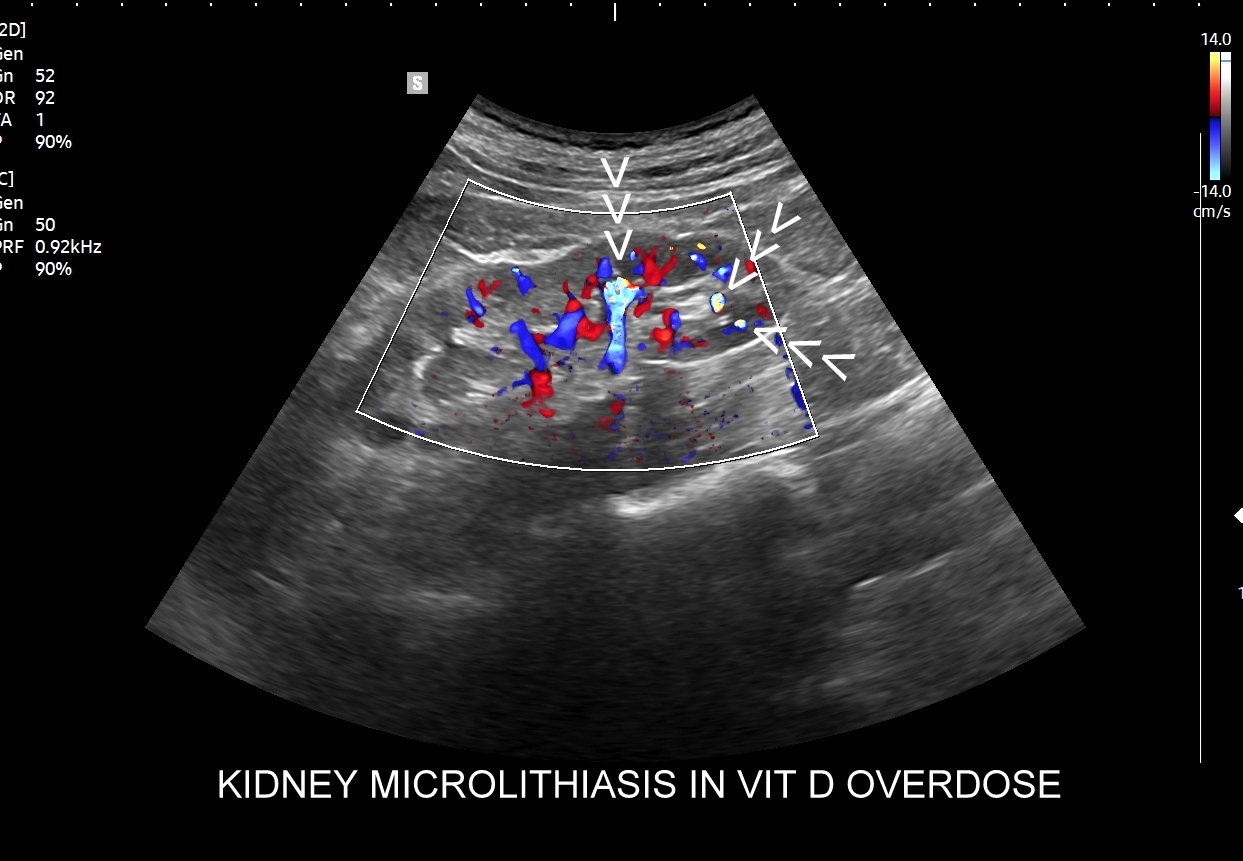

Przyczyny hyperkalcemii i wtórnie hyperkalciurii obejmują zwykle nadczynność przytarczyc, przedawkowanie witaminy D, osteolityczne choroby nowotworowe, długotrwałe unieruchomienie, sarkoidozę. U pacjentów z idiopatycznymi przypadkami kamicy nerkowej w badaniach laboratoryjnych stwierdza się takie zaburzenia jak zwiększone wydalanie z moczem wapnia oraz szczawianów.

Badania obrazowe służące wykrywaniu kamicy moczowej to badanie RTG, CT, lecz przede wszystkim badanie USG. W badaniu USG nerek w prezentacji B kamica nerkowa widoczna jest w sytuacji, gdy złogi są odpowiednio uwapnione, odpowiednio duże oraz nie zlewają się z zatoką tłuszczową miedniczki nerki. Zasadniczo złogi w trybie B będą widoczne wyraźniej, gdy położone są w miąższu nerki; z kolei w miedniczce nerkowej, gdy są na tyle duże, że dają artefakt cienia. Czasem w celu uwidocznienia złogu przydatne jest wyłączenie wspomagania typu x-beam.

Ważnym trybem pomocniczym jest color-Doppler, w którym to trybie uzyskuje się tzw. artefakt migotania, często nawet na bardzo drobnych złogach niewidocznych w trybie B. Uzyskanie efektu migotania jest niestety zależne o jakości aparatury USG, a także od ustawień Dopplera i software’u.